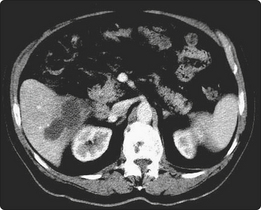

An amoebic liver abscess develops when trophozoites of Entamoeba histolytica ascend from the colon to the portal vein and invade liver tissue (Fig. 3.34.4). Patients present with hepatomegaly, hepatic tenderness and a leukocytosis. A 10 day course of metronidazole is usually sufficient to eliminate the abscess.